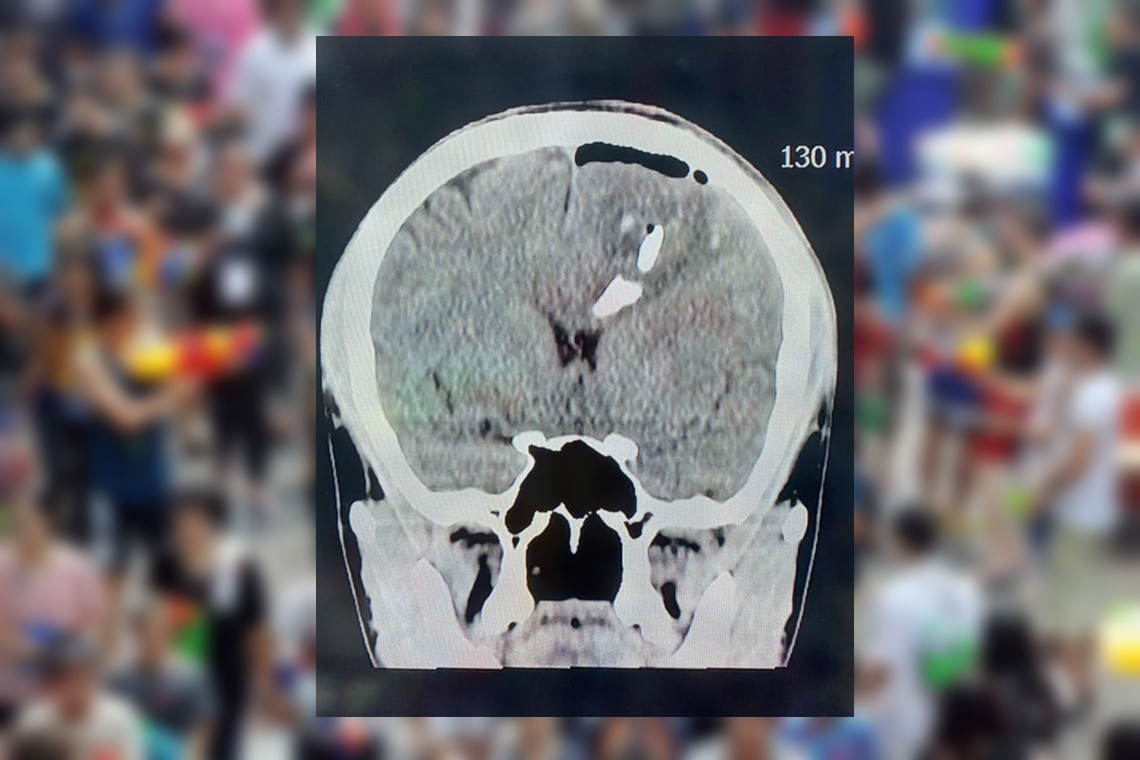

กรณีตัวอย่างผู้ป่วยประสบอุบัติเหตุ ทางสมองอย่างรุนแรง ทำให้กะโหลกศีรษะแตกเป็นชิ้นๆ ฝังลึกเข้าไปในเนื้อสมอง ทำให้มีภาวะเลือดออกในสมอง และเนื้อสมองถูกทำลายไปบางส่วน ผู้ป่วยยังรู้สึกตัว ถูกนำส่งโรงพยาบาลประจวบคีรีขันธ์

หลังจากดูแลเบื้องต้น เอกซเรย์สมอง ปรึกษาแพทย์ผู้เชี่ยวชาญด้านศัลยศาสตร์สมองและระบบประสาท เตรียมตัวผู้ป่วย นำเข้าห้องผ่าตัดทันที

การผ่าตัดสมองค่อนข้างละเอียดอ่อน เพื่อหยุดเลือดที่ออก เอาเศษกระดูก กะโหลกศีรษะ ลิ่มเลือดที่ตกค้างออก เย็บปิดเยื่อหุ้มสมอง การผ่าตัดใช้เวลาประมาณ 1 ชั่วโมง ประสบผลสำเร็จเป็นอย่างดี ประเมินอาการทางสมองหลังผ่าตัดเป็นที่น่าพอใจ